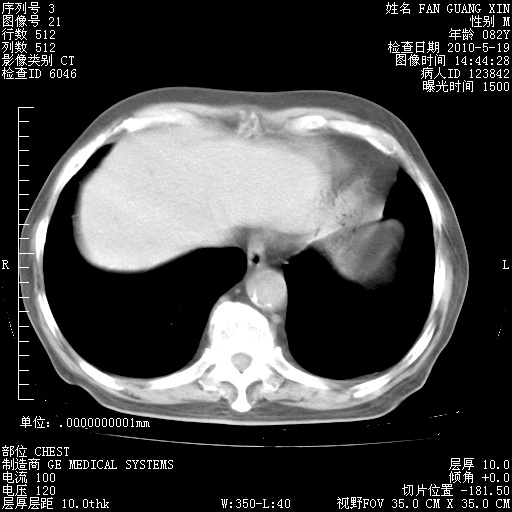

再治疗10天后的肺部CT 纵膈窗

阅读此次胸部CT,肺间质渗出性改变较入院时有吸收。目前从体温、白细胞、中性分叶明显增高,肯定存在细菌感染(发生医院感染哦,若无消化道及泌尿系统等感染的依据,肺部感染可能大)。若你院头孢哌酮舒巴坦钠耐药率较高,同意你的方案,若48小时体温仍高,可考虑使用碳青霉稀类抗菌药物,同时可予超声雾化、注意滴数时加大液体量。白蛋白33.30g/L较低哦,需加强营养等支持治疗。